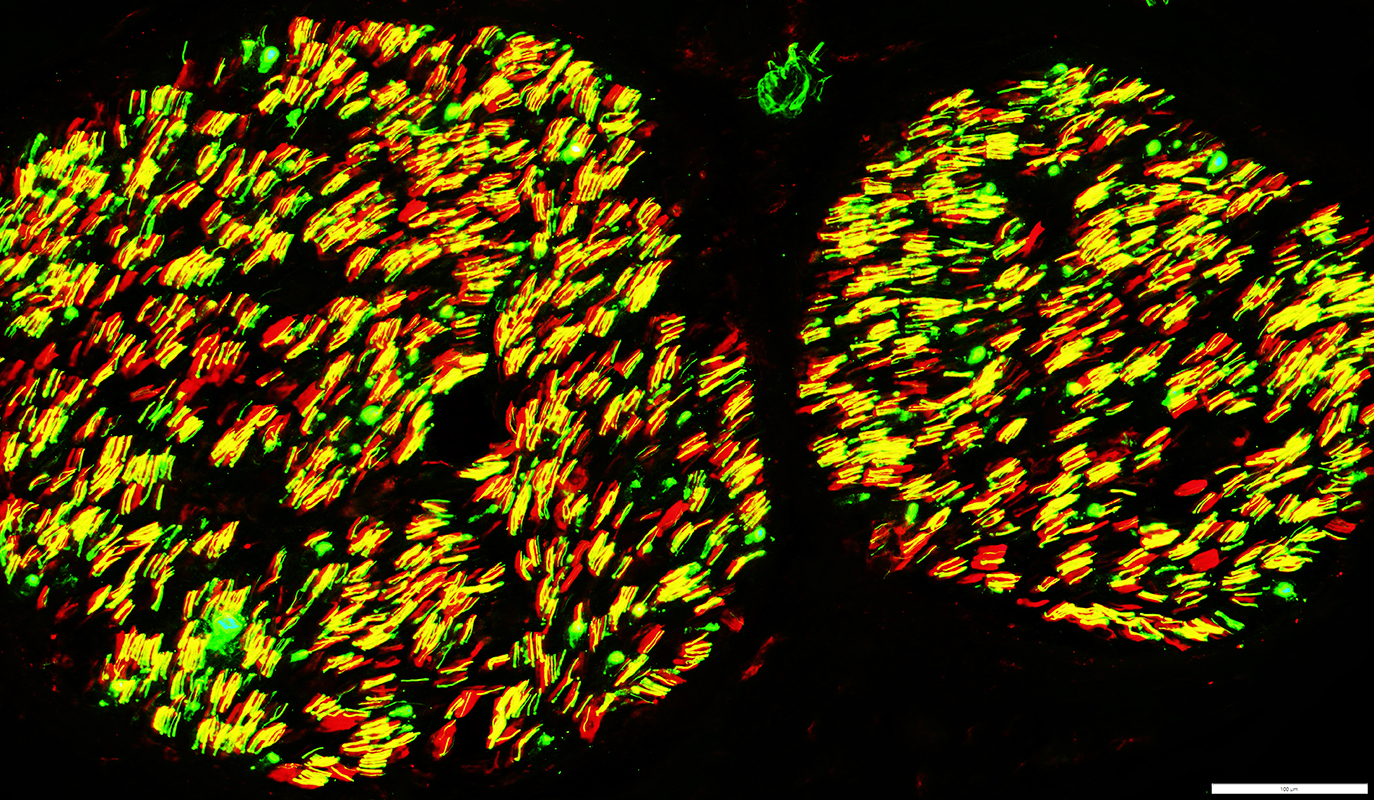

Neurofilament (Green), Myelin basic protein (Red) stain

Neurofilament stained axons in sural nerve (Yellow)

Lost within many MBP stained myelin sheaths (Red)

Unmyelinated Axons: preserved numbers (Green)

Neurofilament stained axons in anterior interosseus nerve (Yellow)

Lost within some MBP stained myelin sheaths (Red)